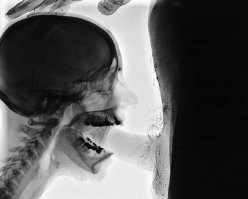

17. "Мой первый рентгеновский снимок на второй день обучения в колледже радиологии"